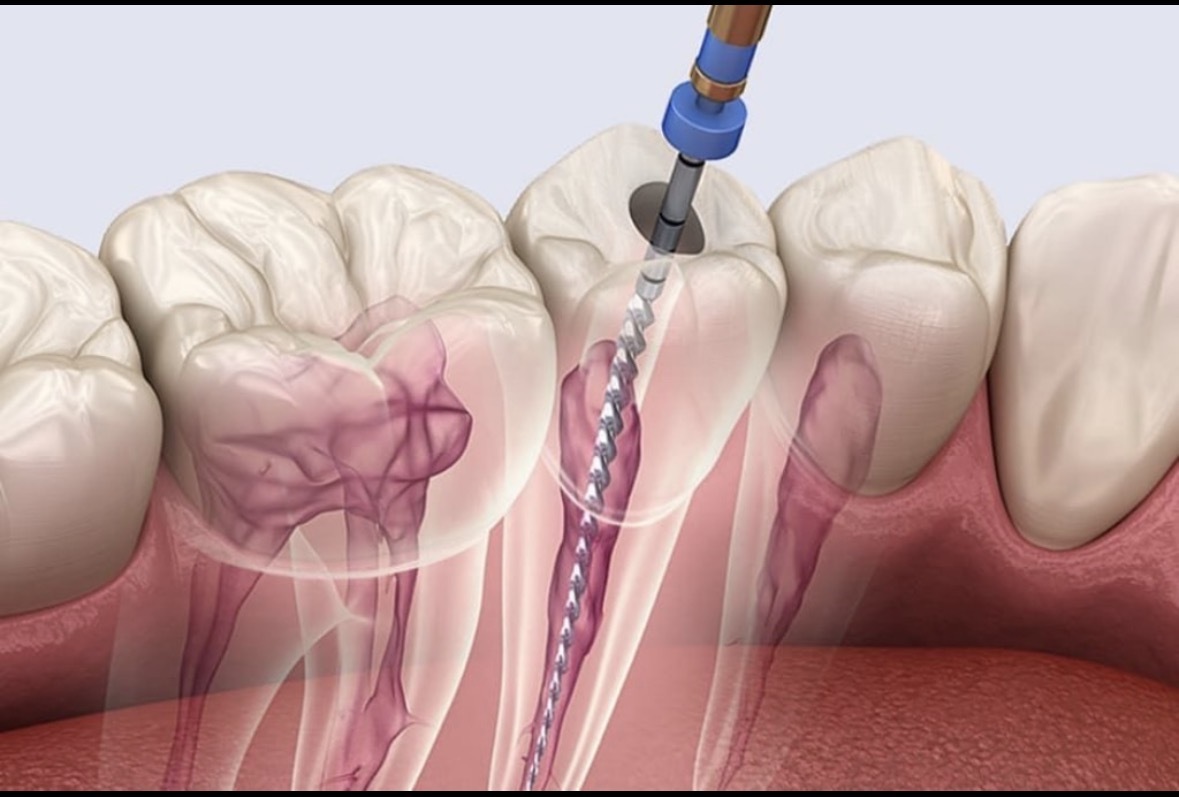

■ 当院の根管治療は“比較的少ない回数”で終わるのが特徴です

とはいえ、必要以上に回数が増えるわけではありません。

伊賀市の当院では、設備と手順を整え、できるだけ短期間で確実に治すことを意識しています。

具体的には…

● 神経を取る治療(初めての根管治療)

➡ 1〜2回で完了するケースがほとんどです。

● 細菌感染がある歯の治療(再治療・根尖病変あり)

➡ 痛みがなければ2〜3回で終わることが多いです。

むやみに回数を増やすのではなく、

「確実に進められるタイミングで、最適な回数で終える」

これが当院の基本方針です。